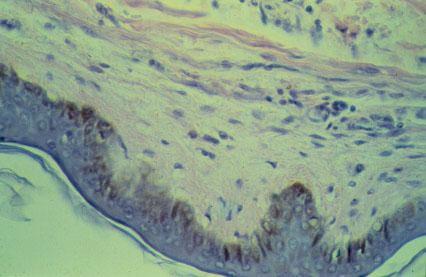

I-31 (4) K Slide 7. Skin epithelium (epidermis) is seen on the bottom. Locate the pigmented cells (rust-brown color).